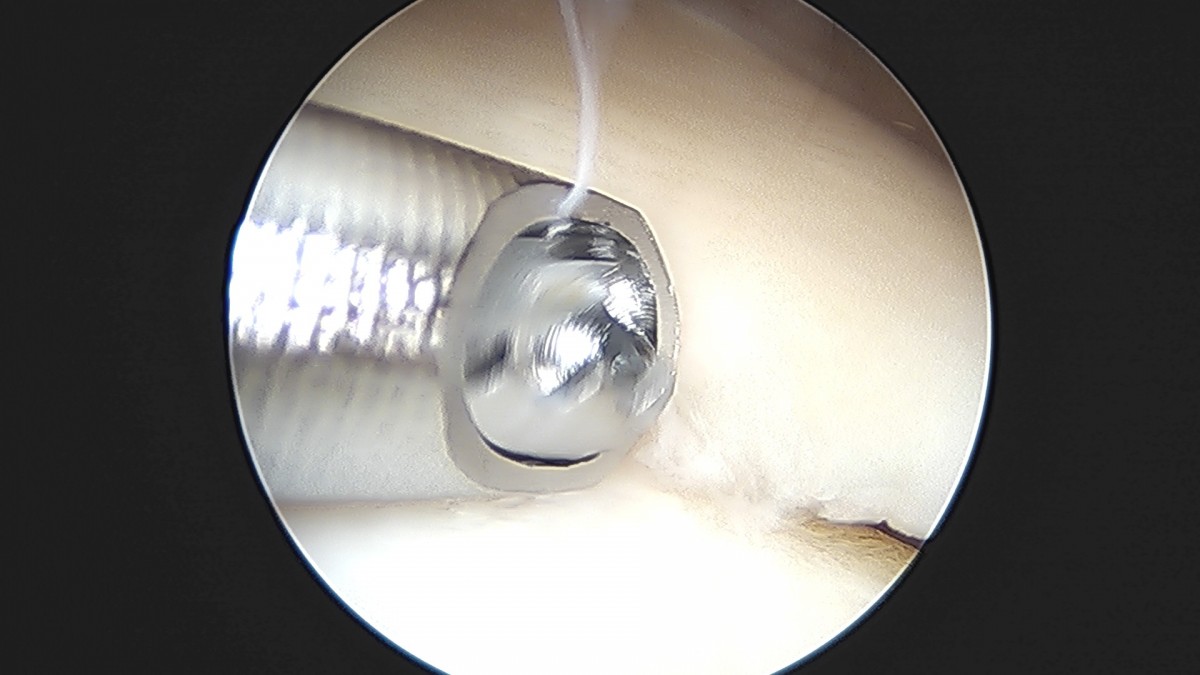

이재상원장님 무릎 반월상 연골판 절제술 박강O 환자

작성자 최고관리자 댓글 0건 조회 381회 작성일 25-09-16 15:47